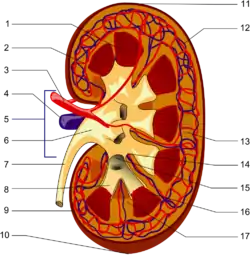

The interlobar arteries are vessels of the renal circulation which supply the renal lobes. The interlobar arteries branch from the lobar arteries which branch from the segmental arteries, from the renal artery. They give rise to arcuate arteries.[1]